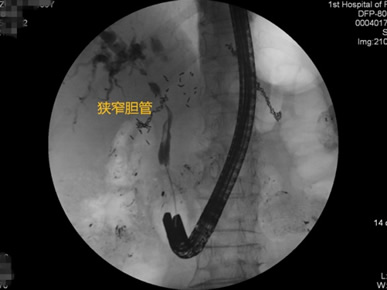

胃毕-Ⅱ术后乳头倒置 胃毕-Ⅱ术后胰管胆管双支架植入 胃毕-Ⅱ术后金属支架植入

胃毕-Ⅱ术后球囊扩张狭窄胆管 胃毕-Ⅱ术后支架植入 胃毕-Ⅱ术后胆管胰管扩张